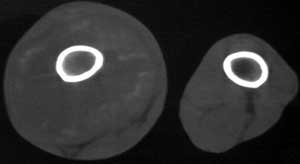

男56涨疼5-6月

右股骨下端包绕股骨见巨大软组织肿块,密度部俊,周围见瘤骨,下端骨皮质侵蚀变薄,骨质周围无骨膜反应, 考虑右股骨软骨肉瘤。

右股骨下段周围软组织肿块伴钙化,相邻股骨骨皮质受累,考虑软组织来源恶性病变

右股骨下段骨肉瘤,软组织内瘤骨,软组织肿块。